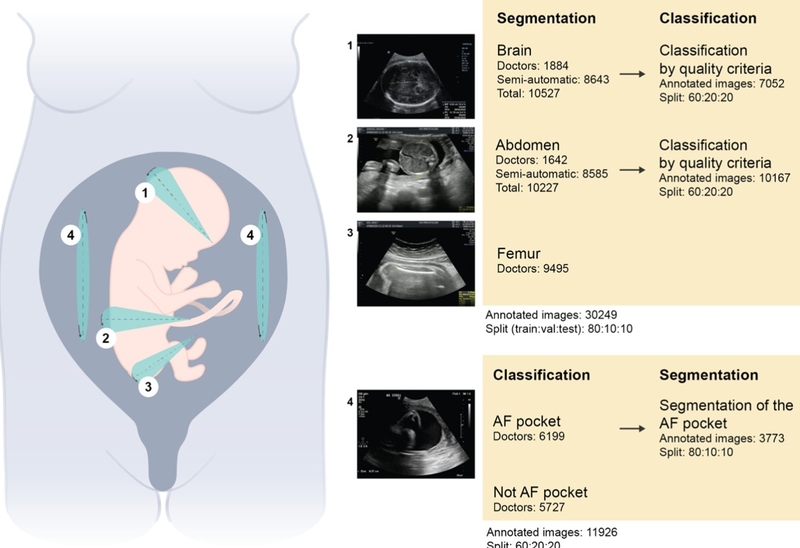

Bên cạnh việc giải đáp thắc mắc LMP là gì, nhiều mẹ bầu cũng phân vân không biết nên đọc kết quả siêu âm như thế nào. Cũng giống các kết quả y khoa khác, kết quả siêu âm thường có rất nhiều chỉ số là thuật ngữ chuyên khoa. Dưới đây là các chỉ số quan trọng trong siêu âm thai bà bầu nên biết.